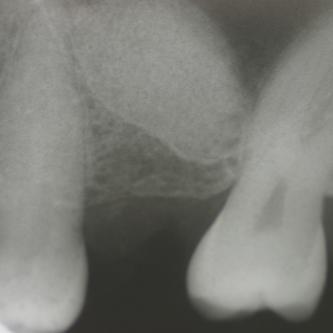

Exemple 14: Il est prévu de mettre un implant entre la molaire et prémolaire, mais le sinus se trouve à moins de 4 mm de la surface. Il faut donc relever le sinus avec une greffe d'os

Exemple 14: Un petit puits d'accès est créé afin d'atteindre le sinus, notez la membrane sinusienne.

Exemple 14: La fine membrane sinusienne est relevée, puis de l'os mélangé à de l'os artificiel est introduit dans la cavité.

Exemple 14: La cavité est maintenant remplie.

Exemple 14: Radiographie post chirurgicale.

Exemple 14: 6 mois plus tard, l'implant est introduit dans cette greffe sans toucher le sinus.